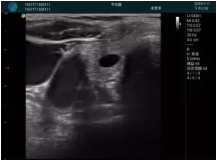

M20查看:囊內(nèi)回聲均勻,邊界清晰,囊壁光滑

M20引導(dǎo)抽吸術(shù)后囊腫消失,原區(qū)域空腔形成,脂肪層與腺體層架構(gòu)發(fā)生改變